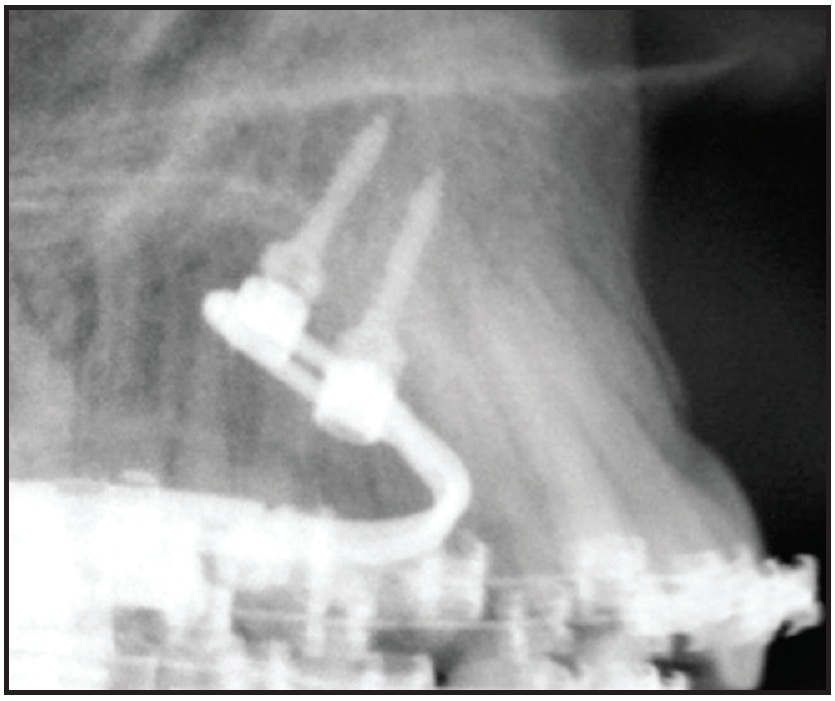

Fig. 2 Cephalogram showing preferred insertion region in anterior palate. Two Benefit mini-implants (anterior, 2mm x 11mm; posterior, 2mm x 9mm) are inserted in line of force.